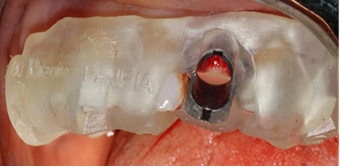

The surgical guide was placed and fixed (Figure 7) and we began the drilling sequence, to place a biotech 3,6/12 implant (Figure 8).

Figure 7. Placement of the surgical guide

Figure 8. Drilling sequence